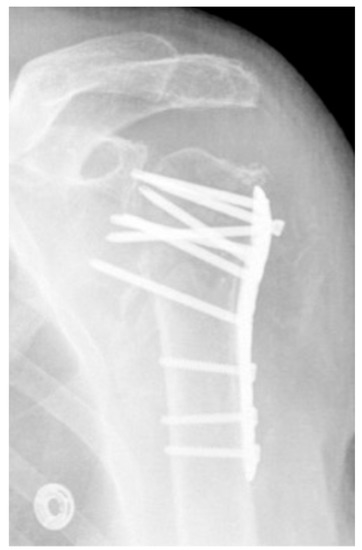

| Complication Type | Exemplary Images by X-rays or Pattern Images | Definition |

|---|---|---|

| 1 | ![]() | Complication Type 1 is defined by a mild, stable varus or valgus displacement (<20°) of the humeral head without resulting in a screw cutout through the humeral head cortex. |